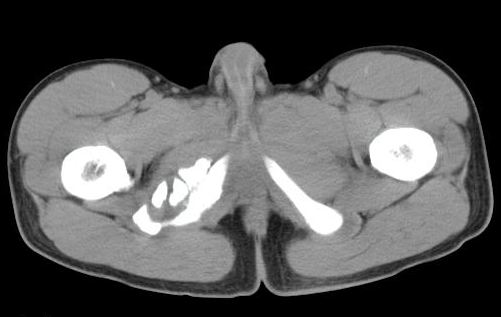

男性,15岁,半年前曾有做运动摔伤史,伤后左肢麻木,一天后恢复,两个月后因右臀部隐痛照片示右坐骨下骨性密度影,现复查见骨性影无明显改变。求助诊断!

坐骨粗大,有瘤骨,基地部有囊状骨缺损。不应为外伤史迷惑,应考虑外生软骨瘤病或骨膜硬纤维瘤。请勿见笑。

坐骨撕脱性骨折伴骨化性肌炎

如果是撕脱骨折,应该有疼痛,而病史是伤后左肢麻木,一天后恢复,两个月后因右臀部隐痛才就诊,病变在肌肉区,故考虑骨化性肌炎

支持坐骨撕脱性骨折合并血肿机化、骨化。

坐骨陈旧性撕脱性粉碎性骨折伴骨痂形成.